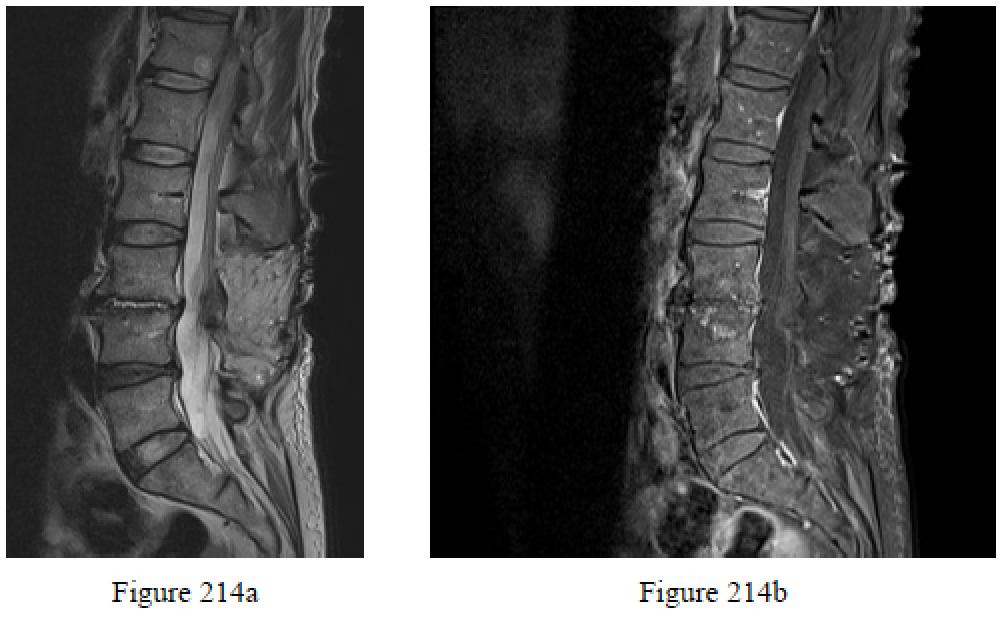

Question 214

Figures 214a and 214b are the sagittal and postcontrast MR images of a 44-year-old man who is admitted to the intensive care unit with severe back pain, fevers, and chills. He has normal strength and sensation. He has elevated erythrocyte sedimentation rate and C-reactive protein levels and negative blood cultures . What is the most appropriate next step?